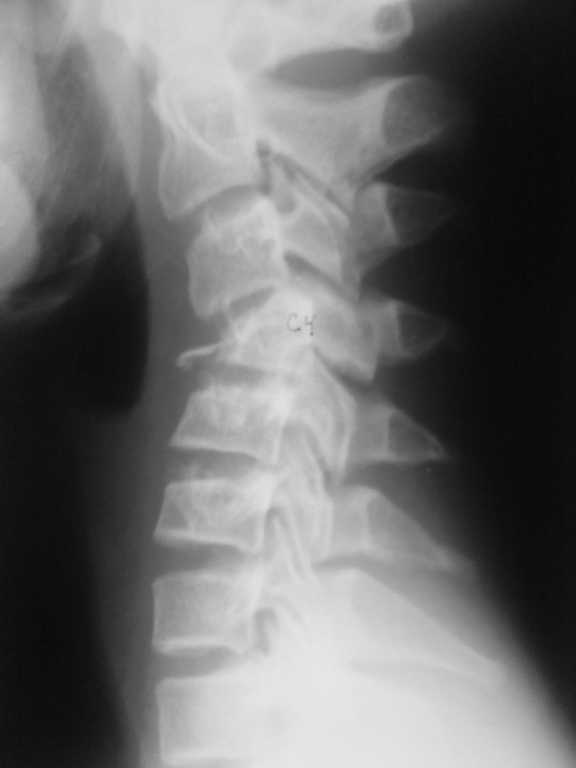

Компрессионный перелом шейного позвонка у подростка

Уважаемые коллеги! Помогите определиться с тактикой лечения. Подросток 14 лет получил травму 2 недели назад , нырнул в реку , вынырнул и на голову прыгнул другой подросток.

Последний госпитализирован в краевую детскую больницу в травматолого-ортопедическое отделение. DS Закрытый нестабильный неосложнённый тип В3 компрессионно- оскольчатый переломо-вывих С4, перелом обеих дужек, перелом сутавного отростка, двухсторонний сцепившийся вывих С4. При поступлении наложен галоапппарат, проводилась галотракция. Представлены Rg-снимки до и после галотракции. Необходимо решить вопрос : необходим ли передний корпородез если да , то когда?

Больному выполнена Rg- ШОП, КТ_ до галотракции, после галотракции.

Судя по тексту сообщений нам представлены результаты исследований до и после галотракции. Их не вижу только я или и еще кто-то? По боковой рентгенограмме и реконструкции КТ спорить о тактике лечения и объеме операции бессмысленно.